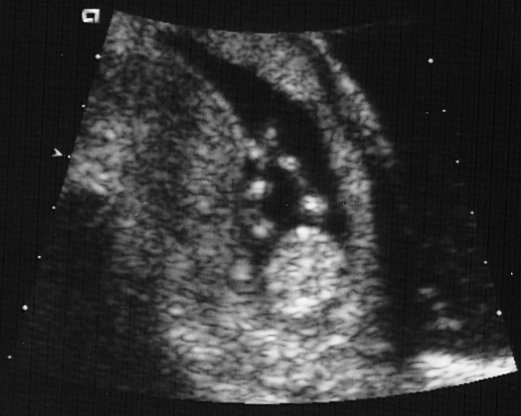

Antes (before)

Futuro padre, Daniel, y madre, Varinia, disfrutan del embarazo, de la buena comida, y de las excusas para dormir, viajar, y hacer nada cada de vez en cuando...

(Future dad, Daniel,  and mother, Varinia, enjoy the pregnancy, the good food, and the excuses to sleep, travel, and do nothing whenever they feel like it...)